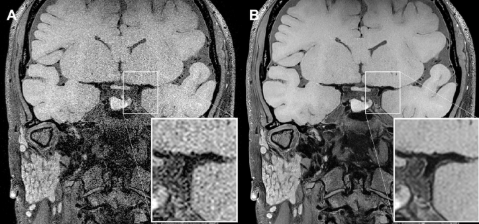

Figura 1: Comparativo de qualidade de imagem: à esquerda, VWI convencional; à direita, VWI aprimorada com SwiftMR, com redução significativa do ruído e maior definição da parede vascular.